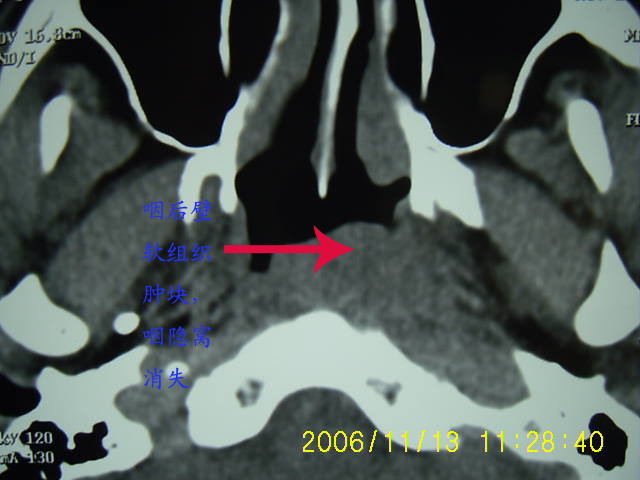

以下是引用刘明在2006-11-13 12:47:00的发言:[br]左侧咽后壁软组织肿块,咽隐窝消失,首先考虑鼻咽癌

以下是引用zyx168在2006-11-13 13:15:00的发言:[br]左侧咽隐窝变浅,咽后壁软组织(头长肌)肿胀,左侧咽旁间隙推移变小.[br]结合临床,双侧颈部淋巴结肿大,考虑为左侧鼻烟癌.